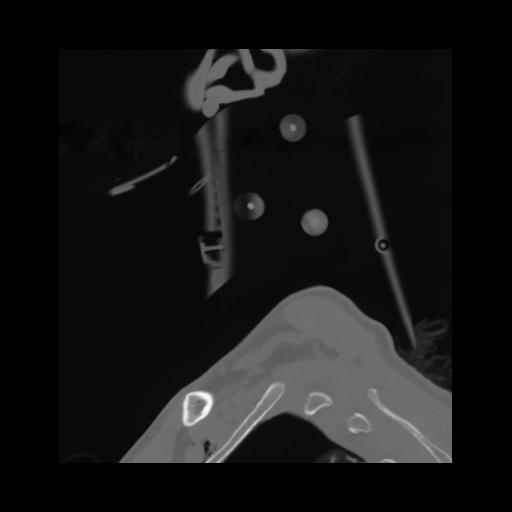

14 P.BLANDAS,,Sagittal,2.000,P.BLANDAS,Sagittal,